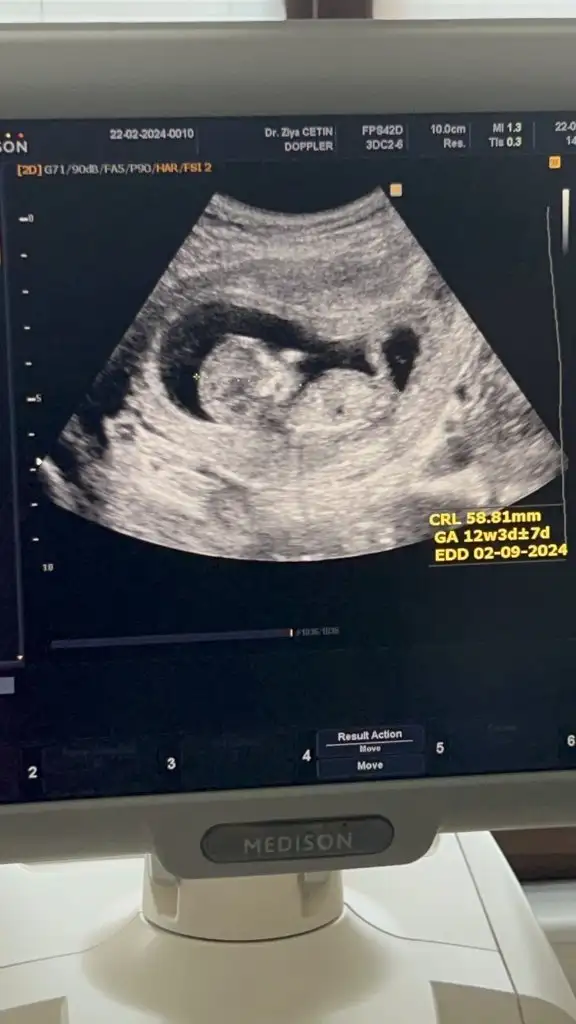

Merhaba, instagramda nereye baktırmıştınız acaba?Ben Instagram dan baktırmıştım, tahminim %70 kız demişti, dün Dr %99 erkek dedi

Bana da bakar mısınKızlar bebişlerinizin ultrason resimlerini ve cinsiyetini kaçıncı haftada olduklarını yazında kendi ultrason resimlerimizle kıyaslayıp fikirde bulunalım. Nub teorisi, kafa şekli, kemik yapısından cinsiyet teorileri tutuyor mu bakalım bir![]()

Banada bakarmısın 11+4 karından ultrasonKızlar bebişlerinizin ultrason resimlerini ve cinsiyetini kaçıncı haftada olduklarını yazında kendi ultrason resimlerimizle kıyaslayıp fikirde bulunalım. Nub teorisi, kafa şekli, kemik yapısından cinsiyet teorileri tutuyor mu bakalım bir![]()